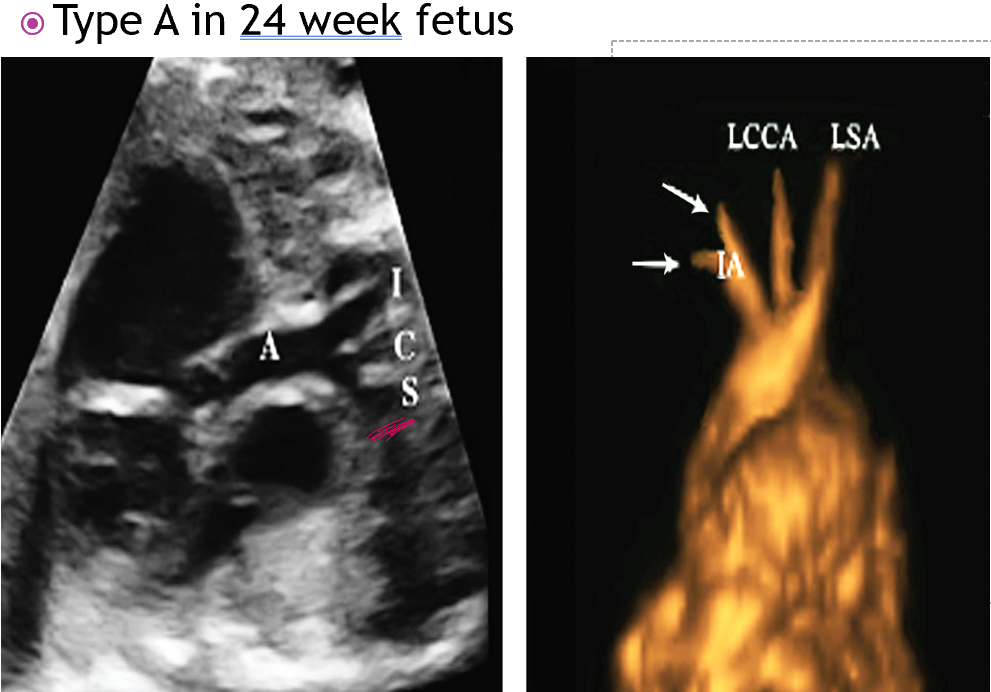

what is interrupted ao arch type A?

interruption found at isthmus

origin of the subclavian artery and the insertion of the ductus arteriosus

distal to left subclavian artery

in type B IAA where is the interruption?

between left subclavian and the LCCA